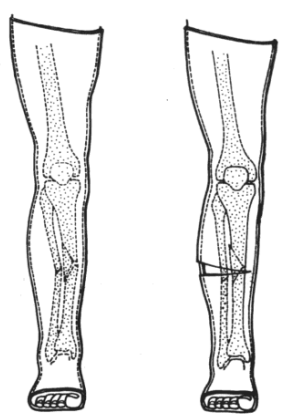

骨折一侧的软组织铰链是维持骨折稳定的重要因素,利用石膏固定骨折时,也必须正确利用这一稳定因素。在存在软组织铰链的对侧为三点固定的中间力点,铰链同侧的骨干上下端各为一个力点(图10)。在石膏管型上只有准确地塑出上述三点关系,才能稳定骨折,单纯依赖石膏管型将上下关节固定住,是不能维持骨折复位位置的。如果不包括上或下关节的石膏也能得到三点固定作用时,当然可以只用石膏局部固定。在石膏硬固前,术者应始终维持其三点应力关系,以防变形失效。

△ 图10 三点固定原则与骨折软组织铰链的关系